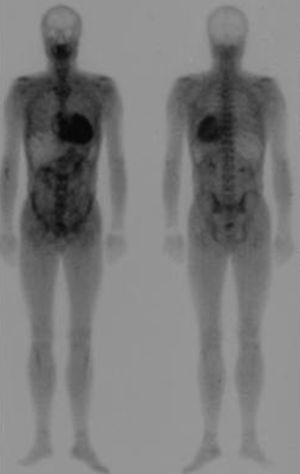

La gammagrafía con tecnecio difosfato (99mTc-DPD) se ha propuesto como una técnica interesante para distinguir entre los depósitos cardiacos de amiloide TTR frente a los de la amiloidosis AL65. Los corazones de los pacientes con amiloidosis TTR (ya sea hereditaria o senil) captarían 99mTc-DPD, mientras que los de aquellos con amiloidosis AL no lo captarían (Figura 5). Tras varios años aplicando esta técnica, hemos comprobado que, cuando la captación es abundante o nula, efectivamente nos permite discriminar las dos etiologías, pero que hasta un tercio de los sujetos con amiloidosis AL presentan captación ligera a nivel cardiaco66.

Figura 5. Gammagrafía con 99mTc-DPD en un paciente con amiloidosis por transtiretina. Se observa intensa captación del radiotrazador a nivel cardiaco con captación ósea atenuada.